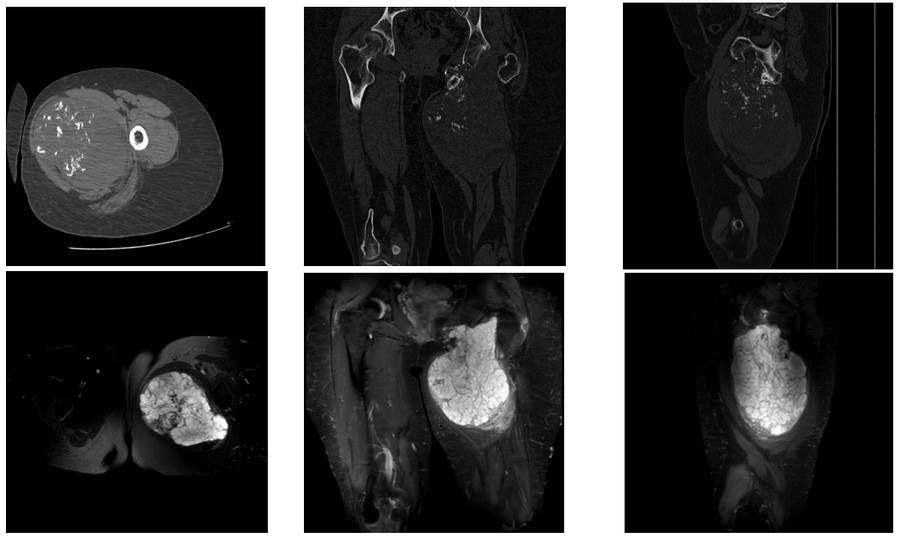

Preoperative examination: CT and MRI scans show a large mass of tissue with irregularly bordered calcification originating from the pubic arm and inferior acetabulum.